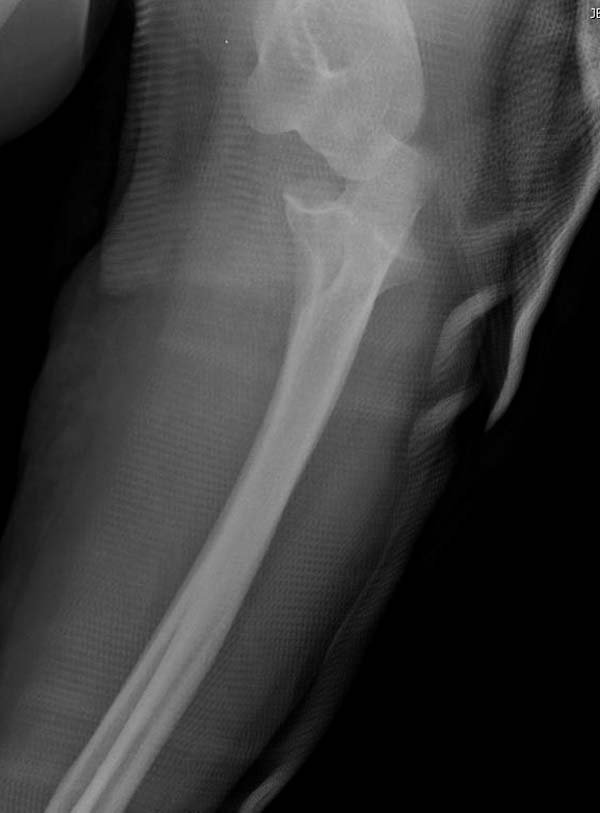

Для примера здесь случай начатый в другом центре, а потом переправленный

к нам.

Снимки: 1-2 вывих, 4-5 вторичное смещение в гипсе, реконструкция

латеральной связки и капсулы 13-14, повторный вывих после реконструкции,